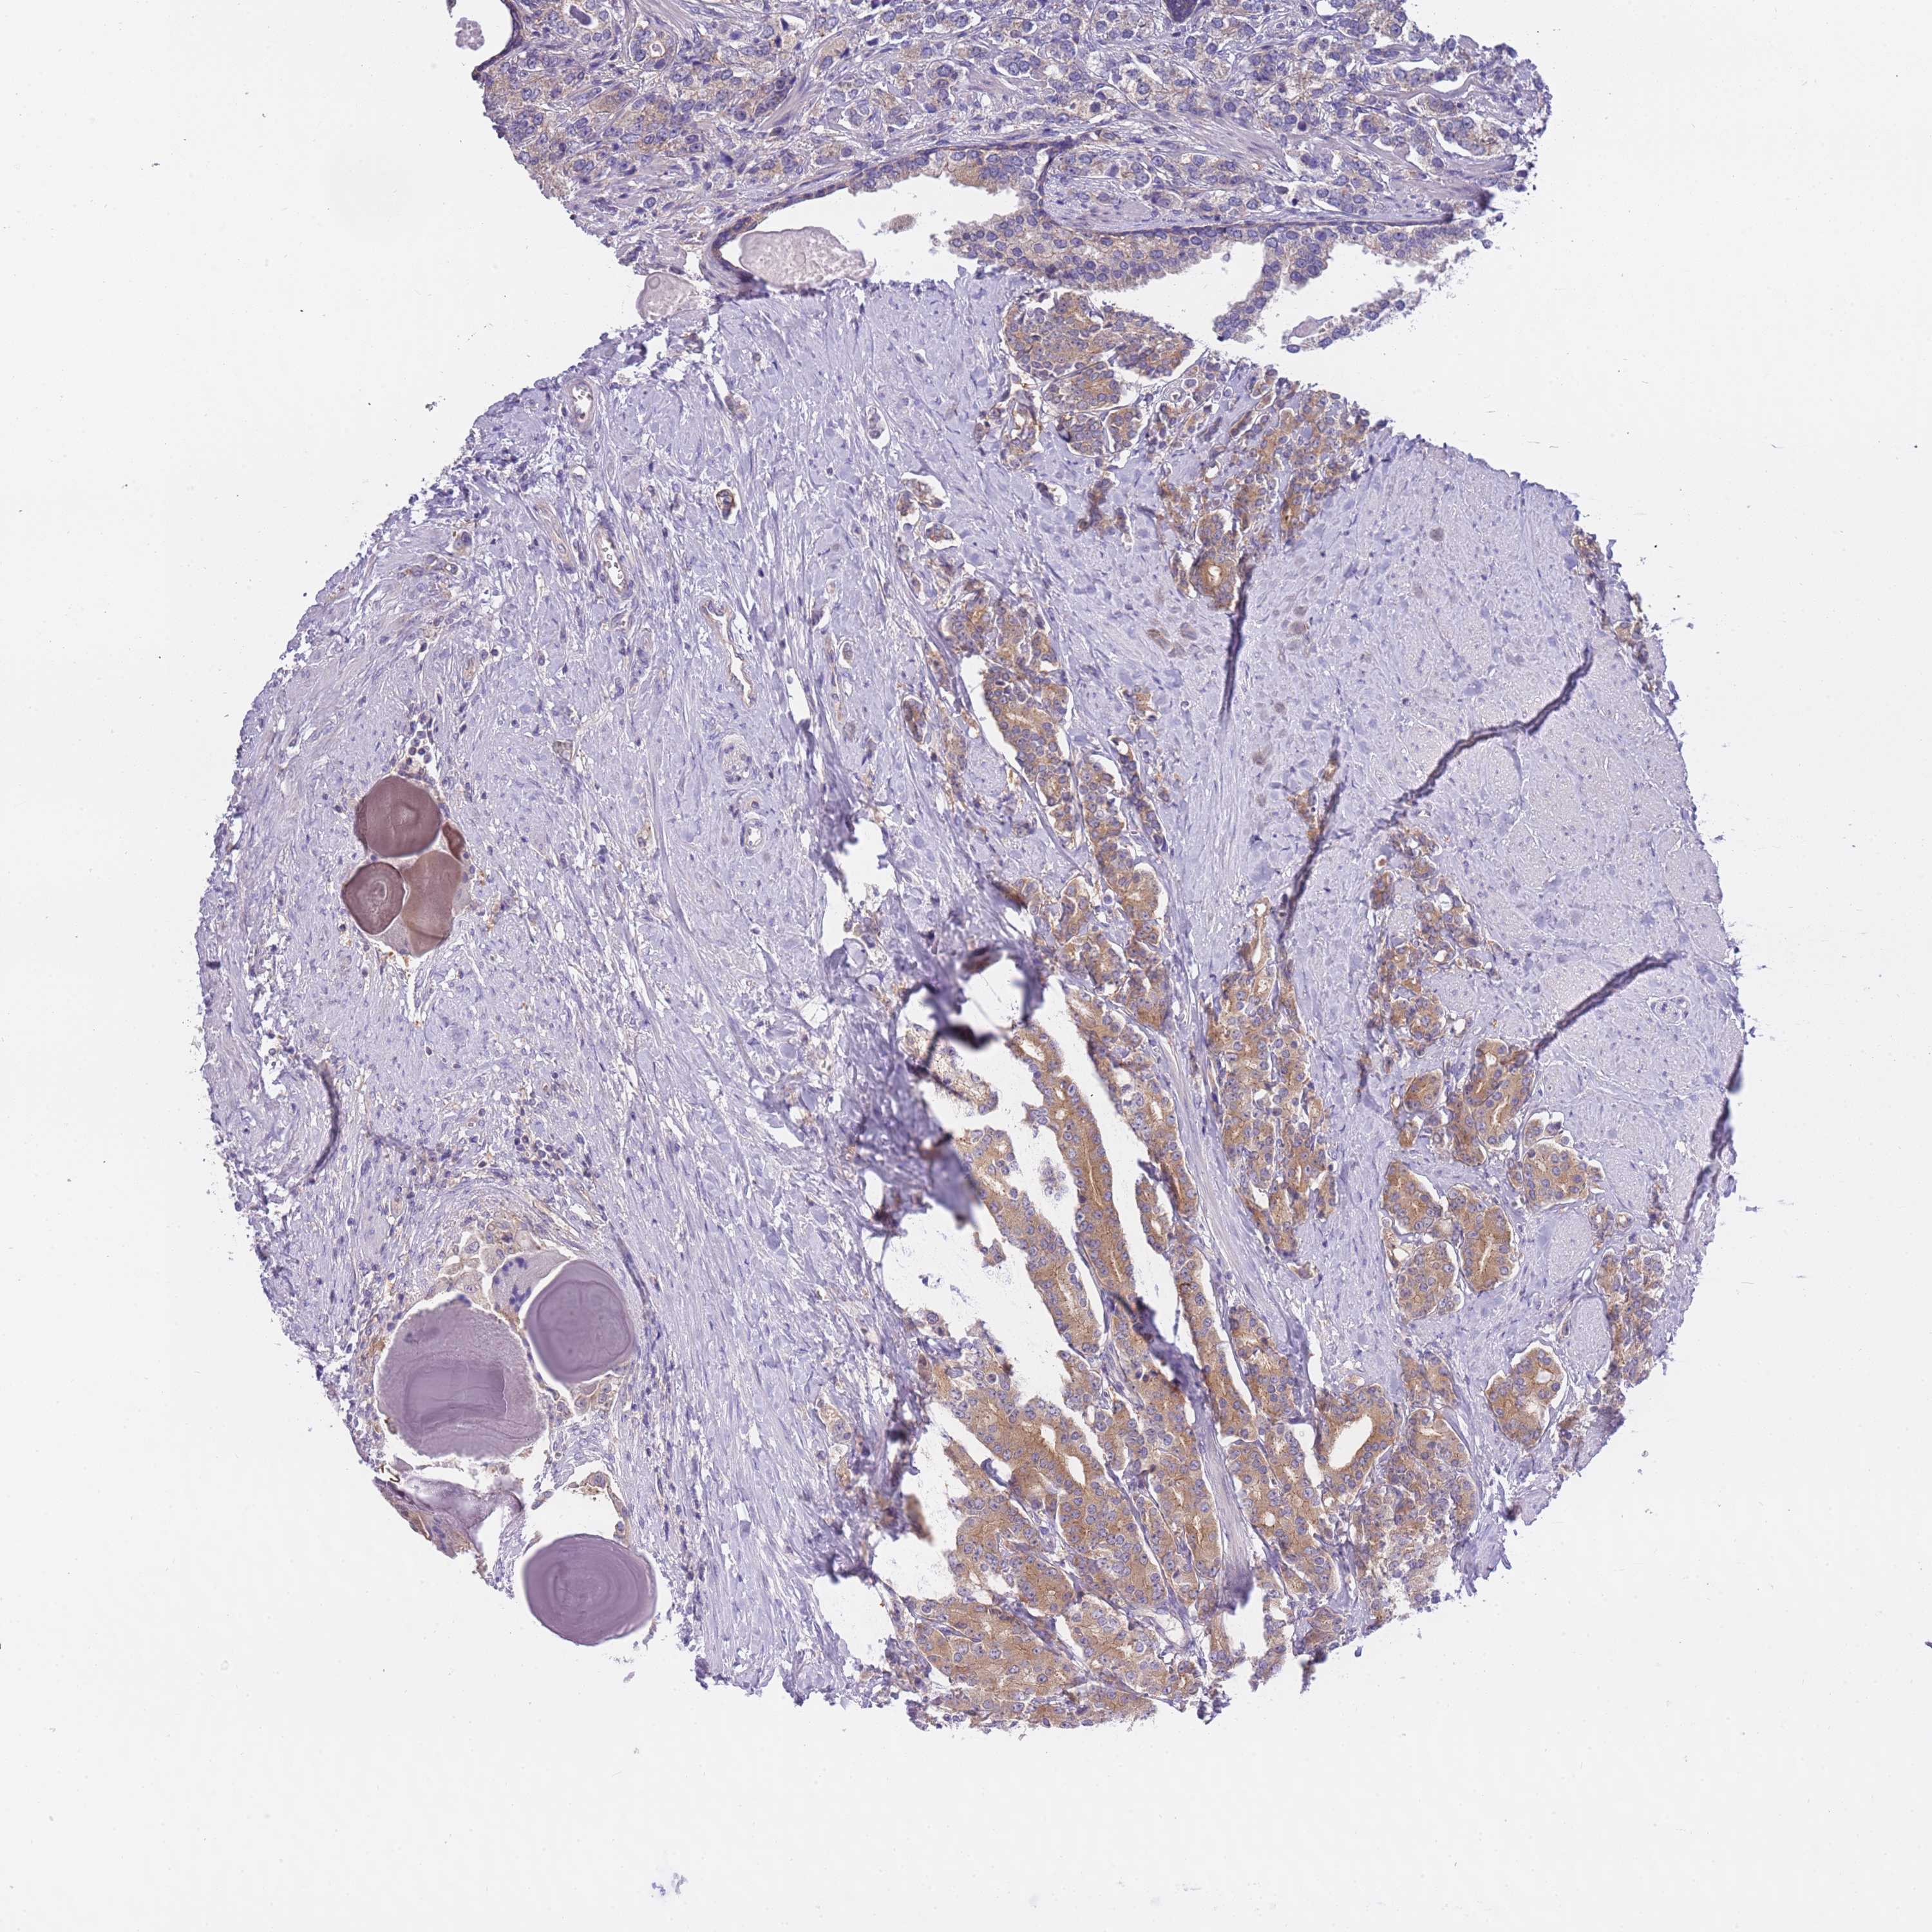

PROSTATE CANCER - Protein expressioni

A mouse-over function shows sample information and annotation data. Click on an image to view it in a full screen mode. Samples can be filtered based on level of antibody staining by selecting one or several of the following categories: high, medium, low and not detected. The assay and annotation is described here.

Antibody stainingi

Antibody staining in the annotated cell types in the current human tissue is reported as not detected, low, medium, or high, based on conventional immunohistochemistry profiling in selected tissues. This score is based on the combination of the staining intensity and fraction of stained cells.

Each image is clickable and will lead to virtual microscopy that enables deeper exploration of all samples and also displays staining intensity scores, fraction scores and subcellular localization as well as patient and tissue information for each sample.

Antibody HPA039291

Antibody HPA044062

Antibody CAB017448

Staining

High

Medium

Low

Not detected

Intensity

Strong

Moderate

Weak

Negative

Quantity

>75%

75%-25%

<25%

None

Location

Nuclear

Cytoplasmic/membranous

Cytoplasmic/membranous,nuclear

Adenocarcinoma, High grade